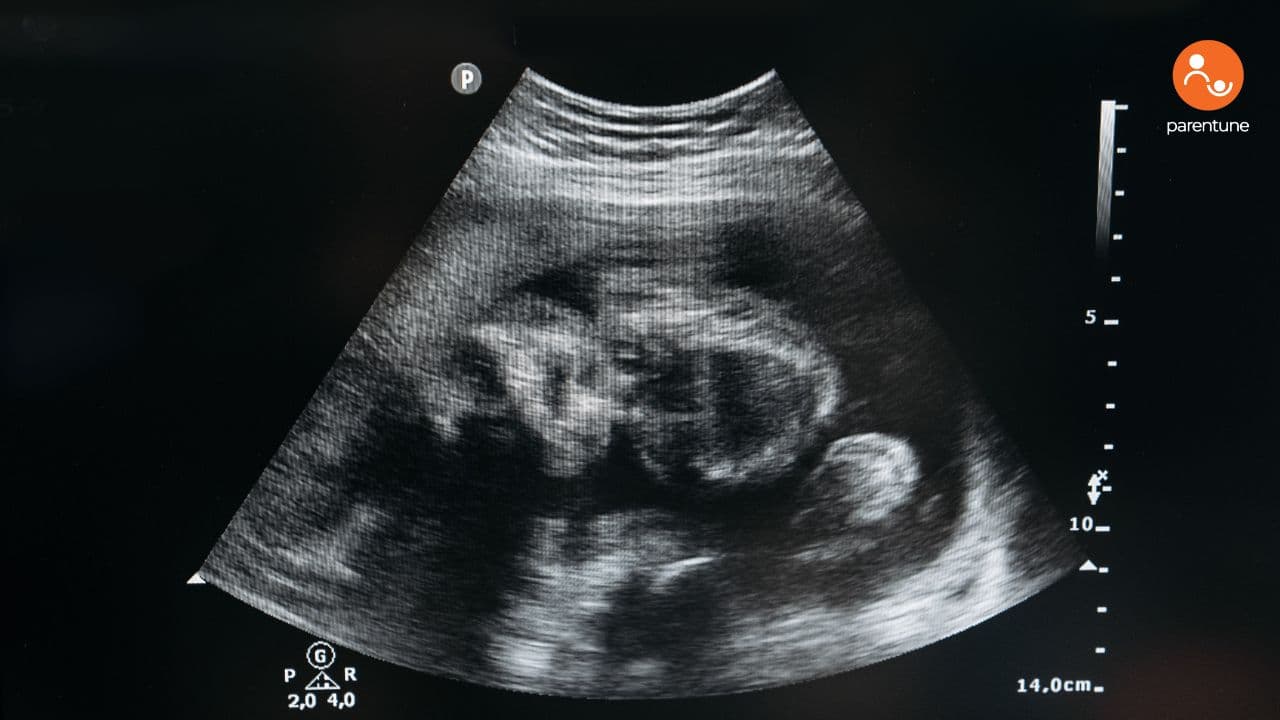

Published: 24/07/25 Updated: 24/07/25 Medical What They Really Mean and Why They Matter You’re lying in bed, hand on belly. And then—there it is. Yes. And no, it’s not weird. Let’s unpack it. What Are Baby Hiccups in the Womb, Really? They’re not hiccups in the adult sense. Fetal hiccups are more like practice drills—tiny spasms of the developing diaphragm. It’s the womb’s version of a sound check before the concert. Why Do Babies Hiccup in the Womb? We don’t have a single reason. We have three strong theories. 1. Breathing Practice 2. Nervous System Development 3. Feeding Reflex Prep So, yes—it’s normal. Recommended Reads: Why Does The Baby Hiccup in The Womb? When Can You Start Feeling Baby Hiccups? Newborn Hiccups: Why They Happen And How To Help How To Get Rid Of Baby Hiccups When Do Hiccups Happen Most Often? You’ll likely notice them: